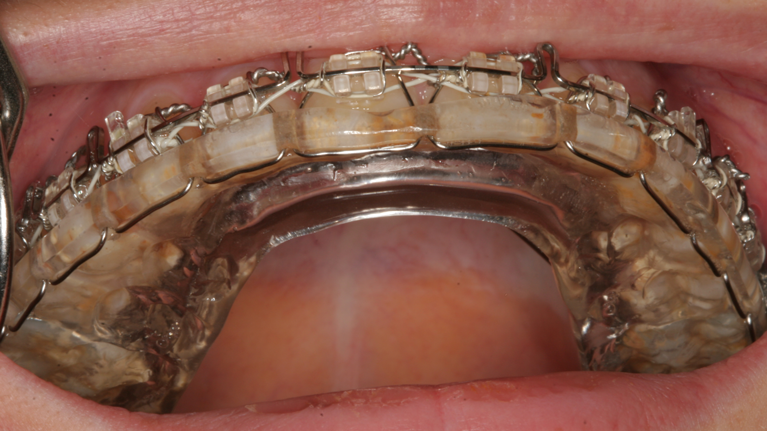

Wafer er en hård skinne af plastik, som fastgøres med ståltråd på bøjlen i din overkæbe under operationen. De fleste har wafer på efter operationen. Skinnen bruges til at stabilisere dit sammenbid.

Du skal regne med at have Wafer på i 6 uger. Det er bøjletandlægen som skal fjerne den, og det foregår uden ubehag.